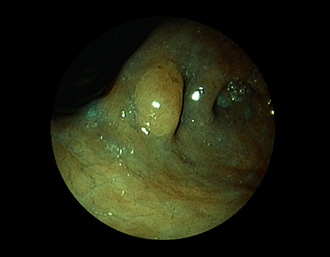

症例5:胃腺腫(84才女性)

胃角部に、大きさ10mm強のなだらかな粘膜隆起を認める。生検:Tubularadenoma with moderate atypia.Group 3。経過観察中。